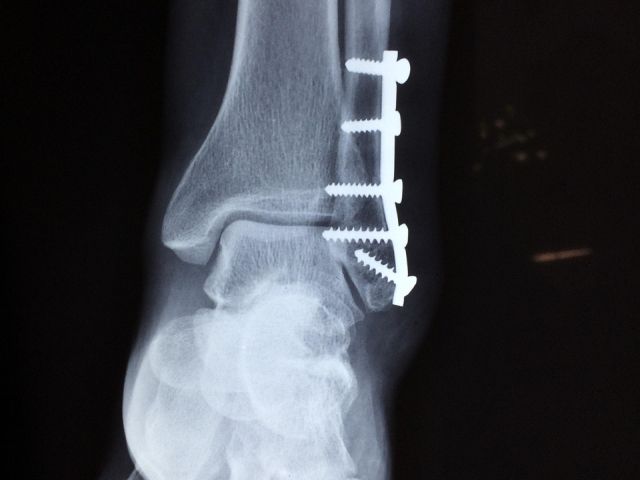

»Predvsem zaradi nadpovprečnega števila zlomov, ki so posledica padcev na spolzkih tleh. Urgentni center Celje še naprej vzdržuje višjo stopnjo pripravljenosti in okrepljene ekipe, vendar pozivamo vse, da pred obiskom urgentnega centra tehtno presodite nujnost obiska urgentnega centra,« pojasnjujejo v bolnišnici.